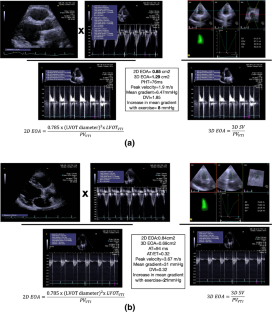

Fig. 1

Fig. 2

Fig. 3

Fig. 4